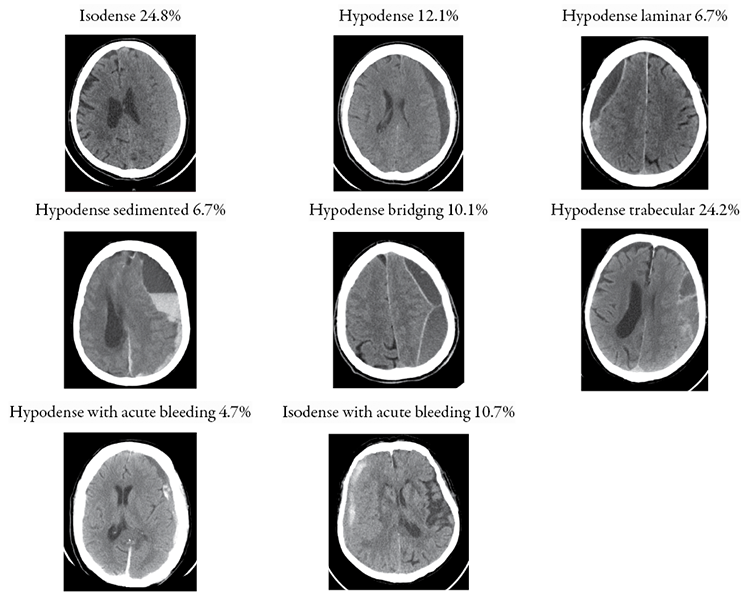

Each hematoma was classified according to one of four Nakaguchi subtypes (homogenous, laminar, separated, trabecular type) as described in the original publication [2]. Additionally, The Nakaguchi classification was extended to accommodate all encountered hematomas. Eight distinct subtypes based on hematoma density and internal hematoma architecture as seen in CT imaging in Figure 1 were defined.

Figure 1. Different subtypes of SSDH and CSDH based on CT imaging

Description of each is as follows: 1) homogenous isodense hematomas: those that are isodense compared to brain tissue; (2) homogenous hypodense hematomas: those that exhibit low density compared to the brain tissue; (3) hypodense laminar: a thin hyperdense visceral or parietal layer (membrane) is visible; (4) hypodense sedimented: different densities within a single hematoma cavity with a clear sedimentation border; (5) hypodense bridging: countable number of internal membranes that connect the visceral and parietal membranes; (6) hypodense trabecular type: uncountable and more complex diffuse inhomogeneous high-density septae between visceral and parietal membranes; (7) hypodense with acute bleeding: chronic subdural hematoma with small hyperdense acute blood components with or without visceral/parietal membranes; (8) isodense with acute bleeding: subacute subdural hematoma with small hyperdense acute blood components with or without visceral/parietal membranes.